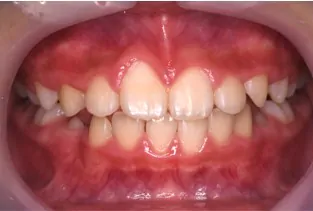

インビザライン・ファーストで対応できる症例

Before

使用中

After

症例の概要

全部で20枚のマウスピースを、1日16時間以上使用していただき、1枚を5日で交換していただき、約3ヶ月でここまで改善しました。

改善したのは前歯の噛み合わせと、奥歯が狭かったので、アーチを広げる事で永久歯が生えるスペースを作りました。

この後は永久歯の生え方等の経過を見ながら、必要に応じてマウスピースを作製し(インビザライン・ファーストは矯正開始から3年間無料で作製できます)歯並びを改善していきます。